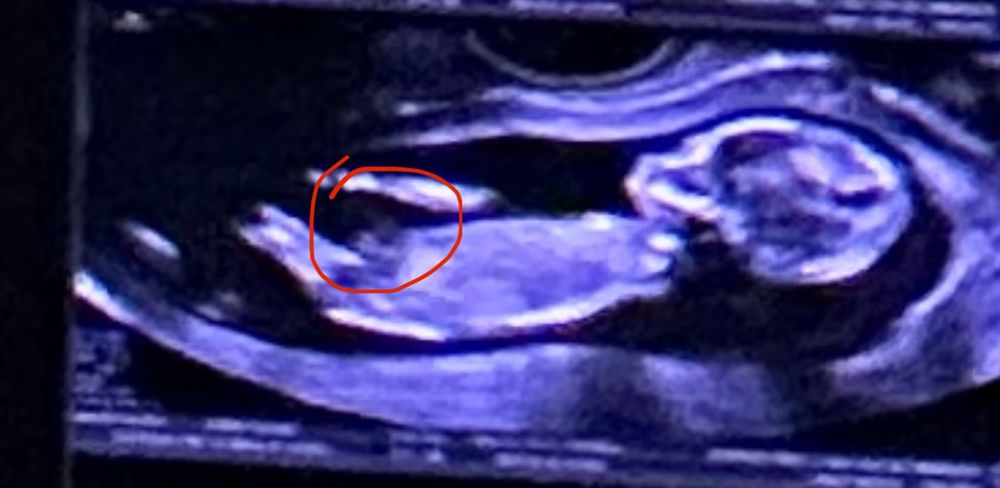

Половой бугорок?

Мальчик 👦

Мне кажется на девочку больше похоже. По крайней мере, у моей в 12 недель было очень похоже. Предположили процентов 70, что девочка, так и оказалась. Но, конечно, на таком сроке всё так не точно.

По мне так девочка.

Похоже что мальчик.Мне тоже предположили мальчика в 12,5 недель ,так и остался мальчик

У девочек совсем не торчит, а идёт параллельно телу. Но с такого ракурса трудно определить. У меня так и нет фото с половым бугорком, малыш ножкой закрыл. Врач мельком увидела, сказала, что мальчик будет.

Юлия , если то, что вы отметили - это бугорок, то мальчик. Мне кажется, это не бугорок, хотя 🧐 А есть фото с 6-7 недель?

Определить пол Мальчик или девочка в 12 недель?